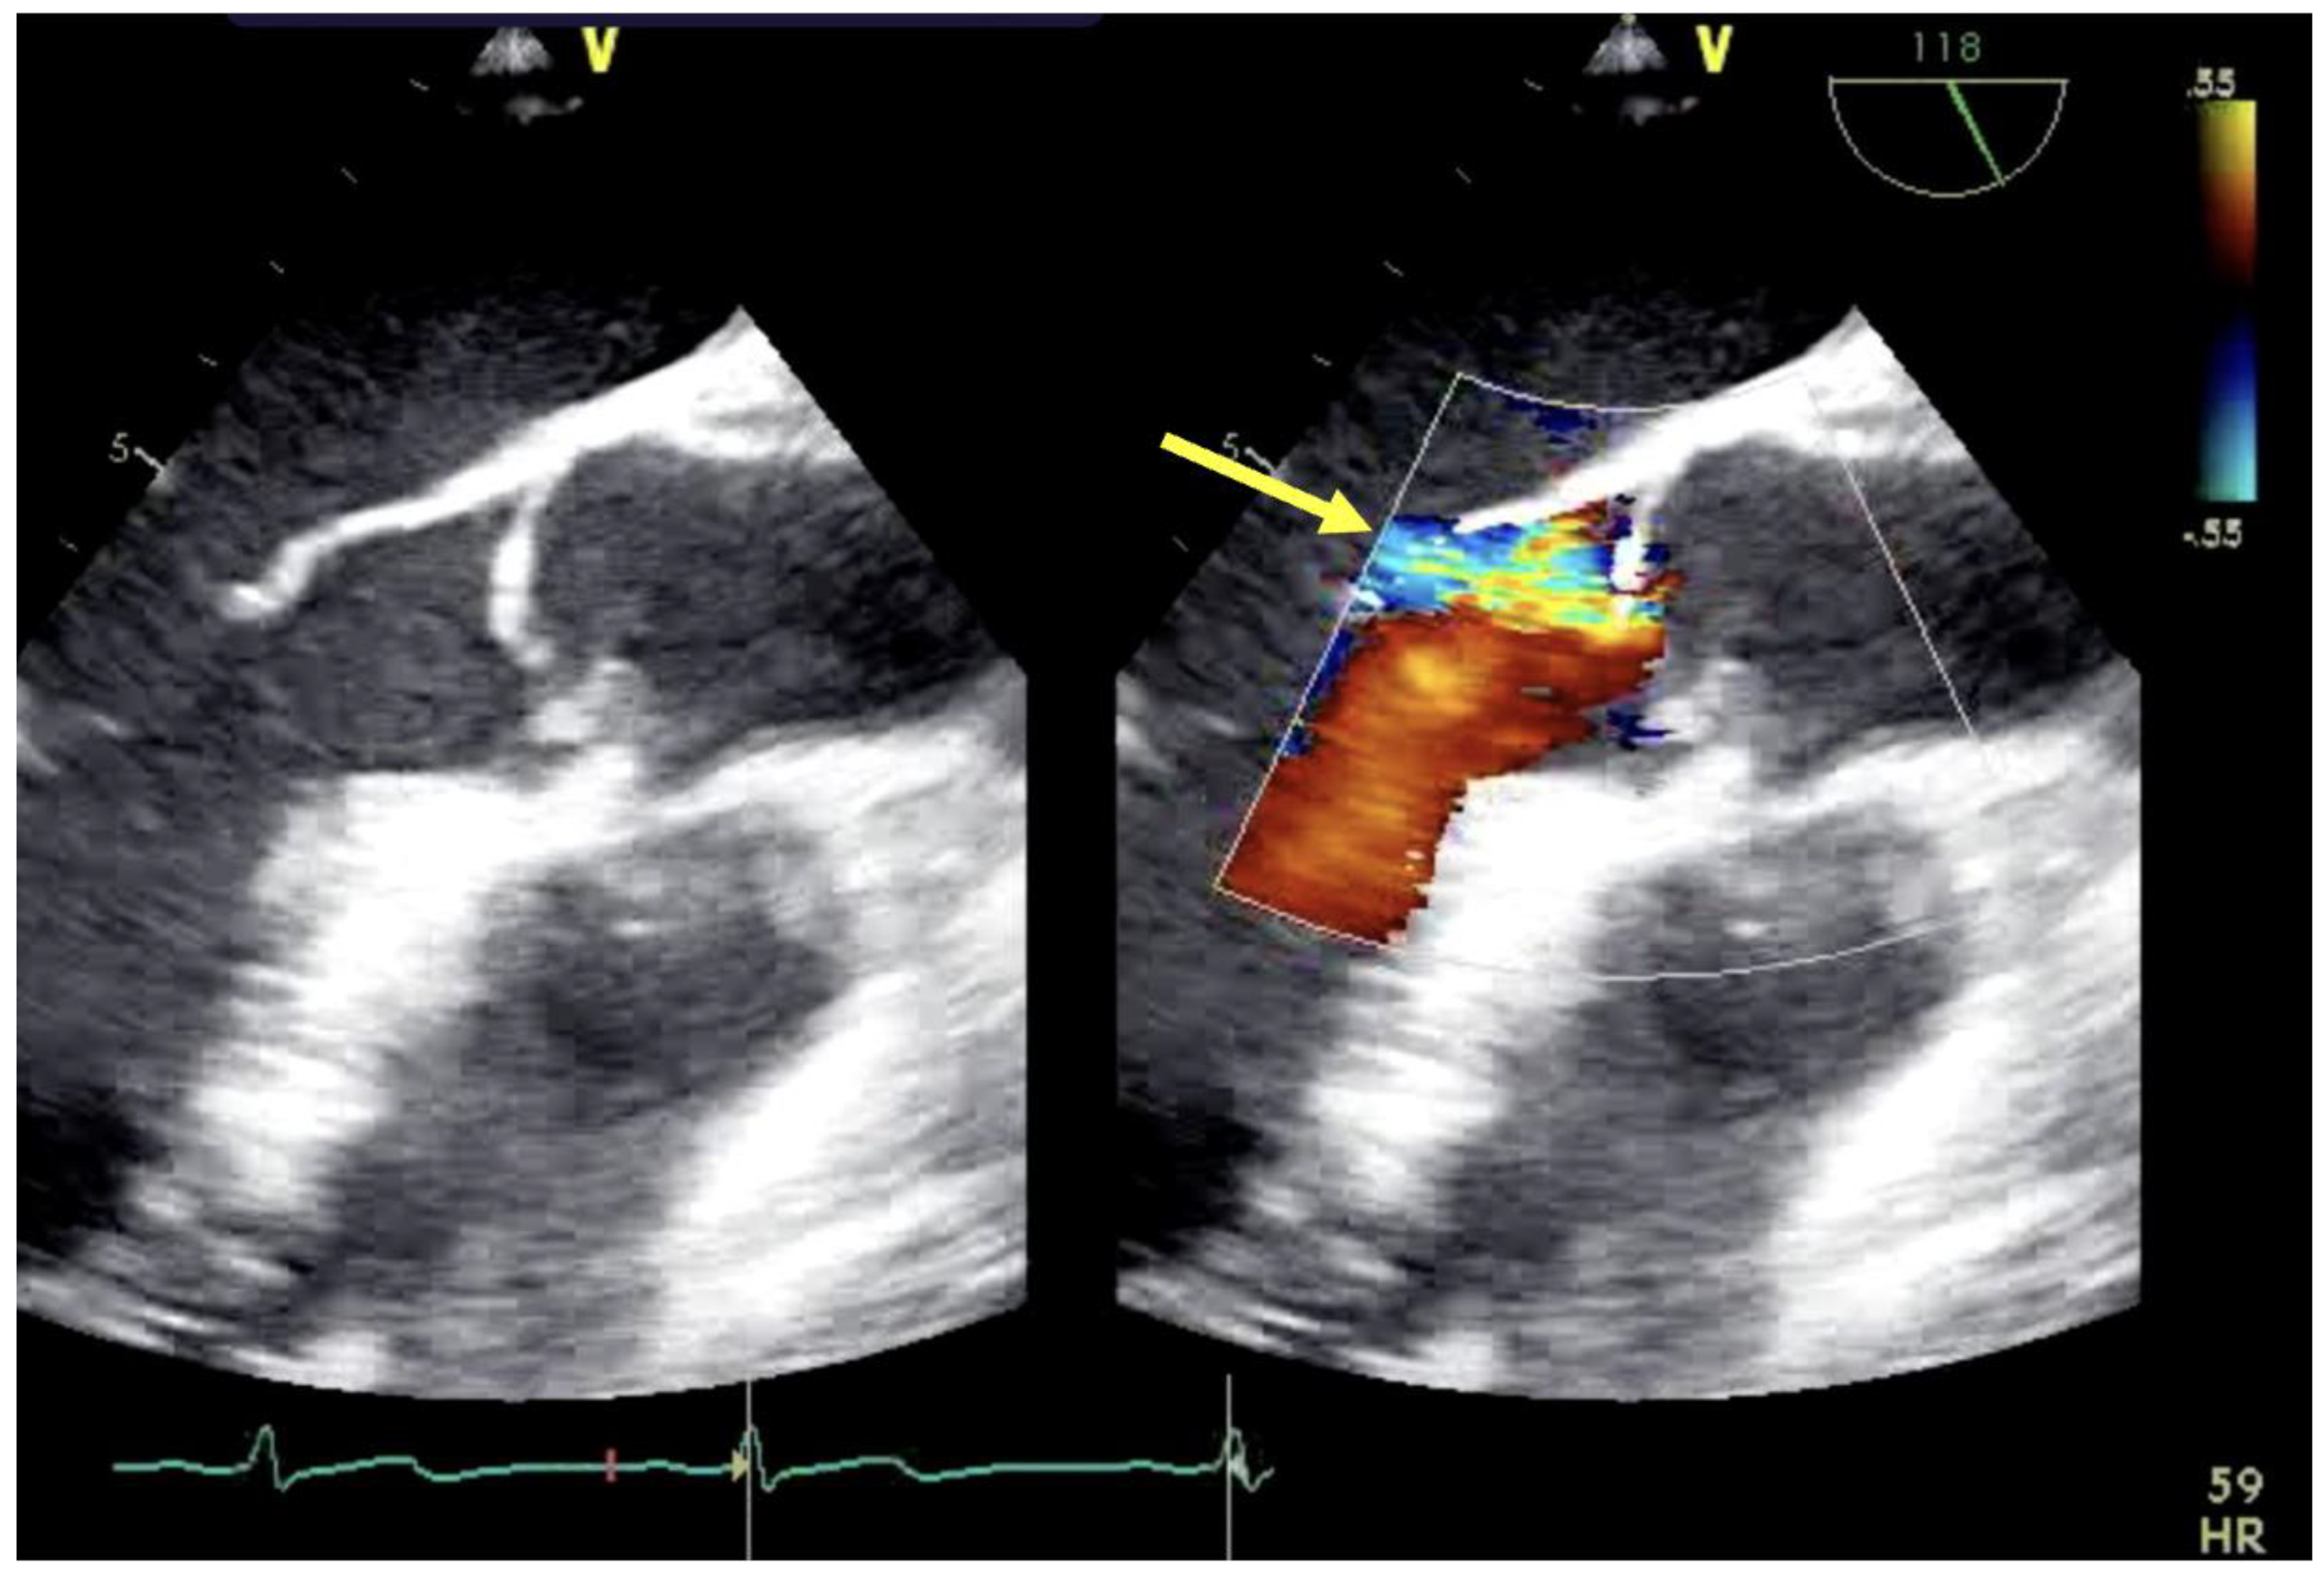

| Assessment of peripheral vasculature for size, disease, thrombus | Assessment of return (outflow) “jet” | Confirmation of cannula position |